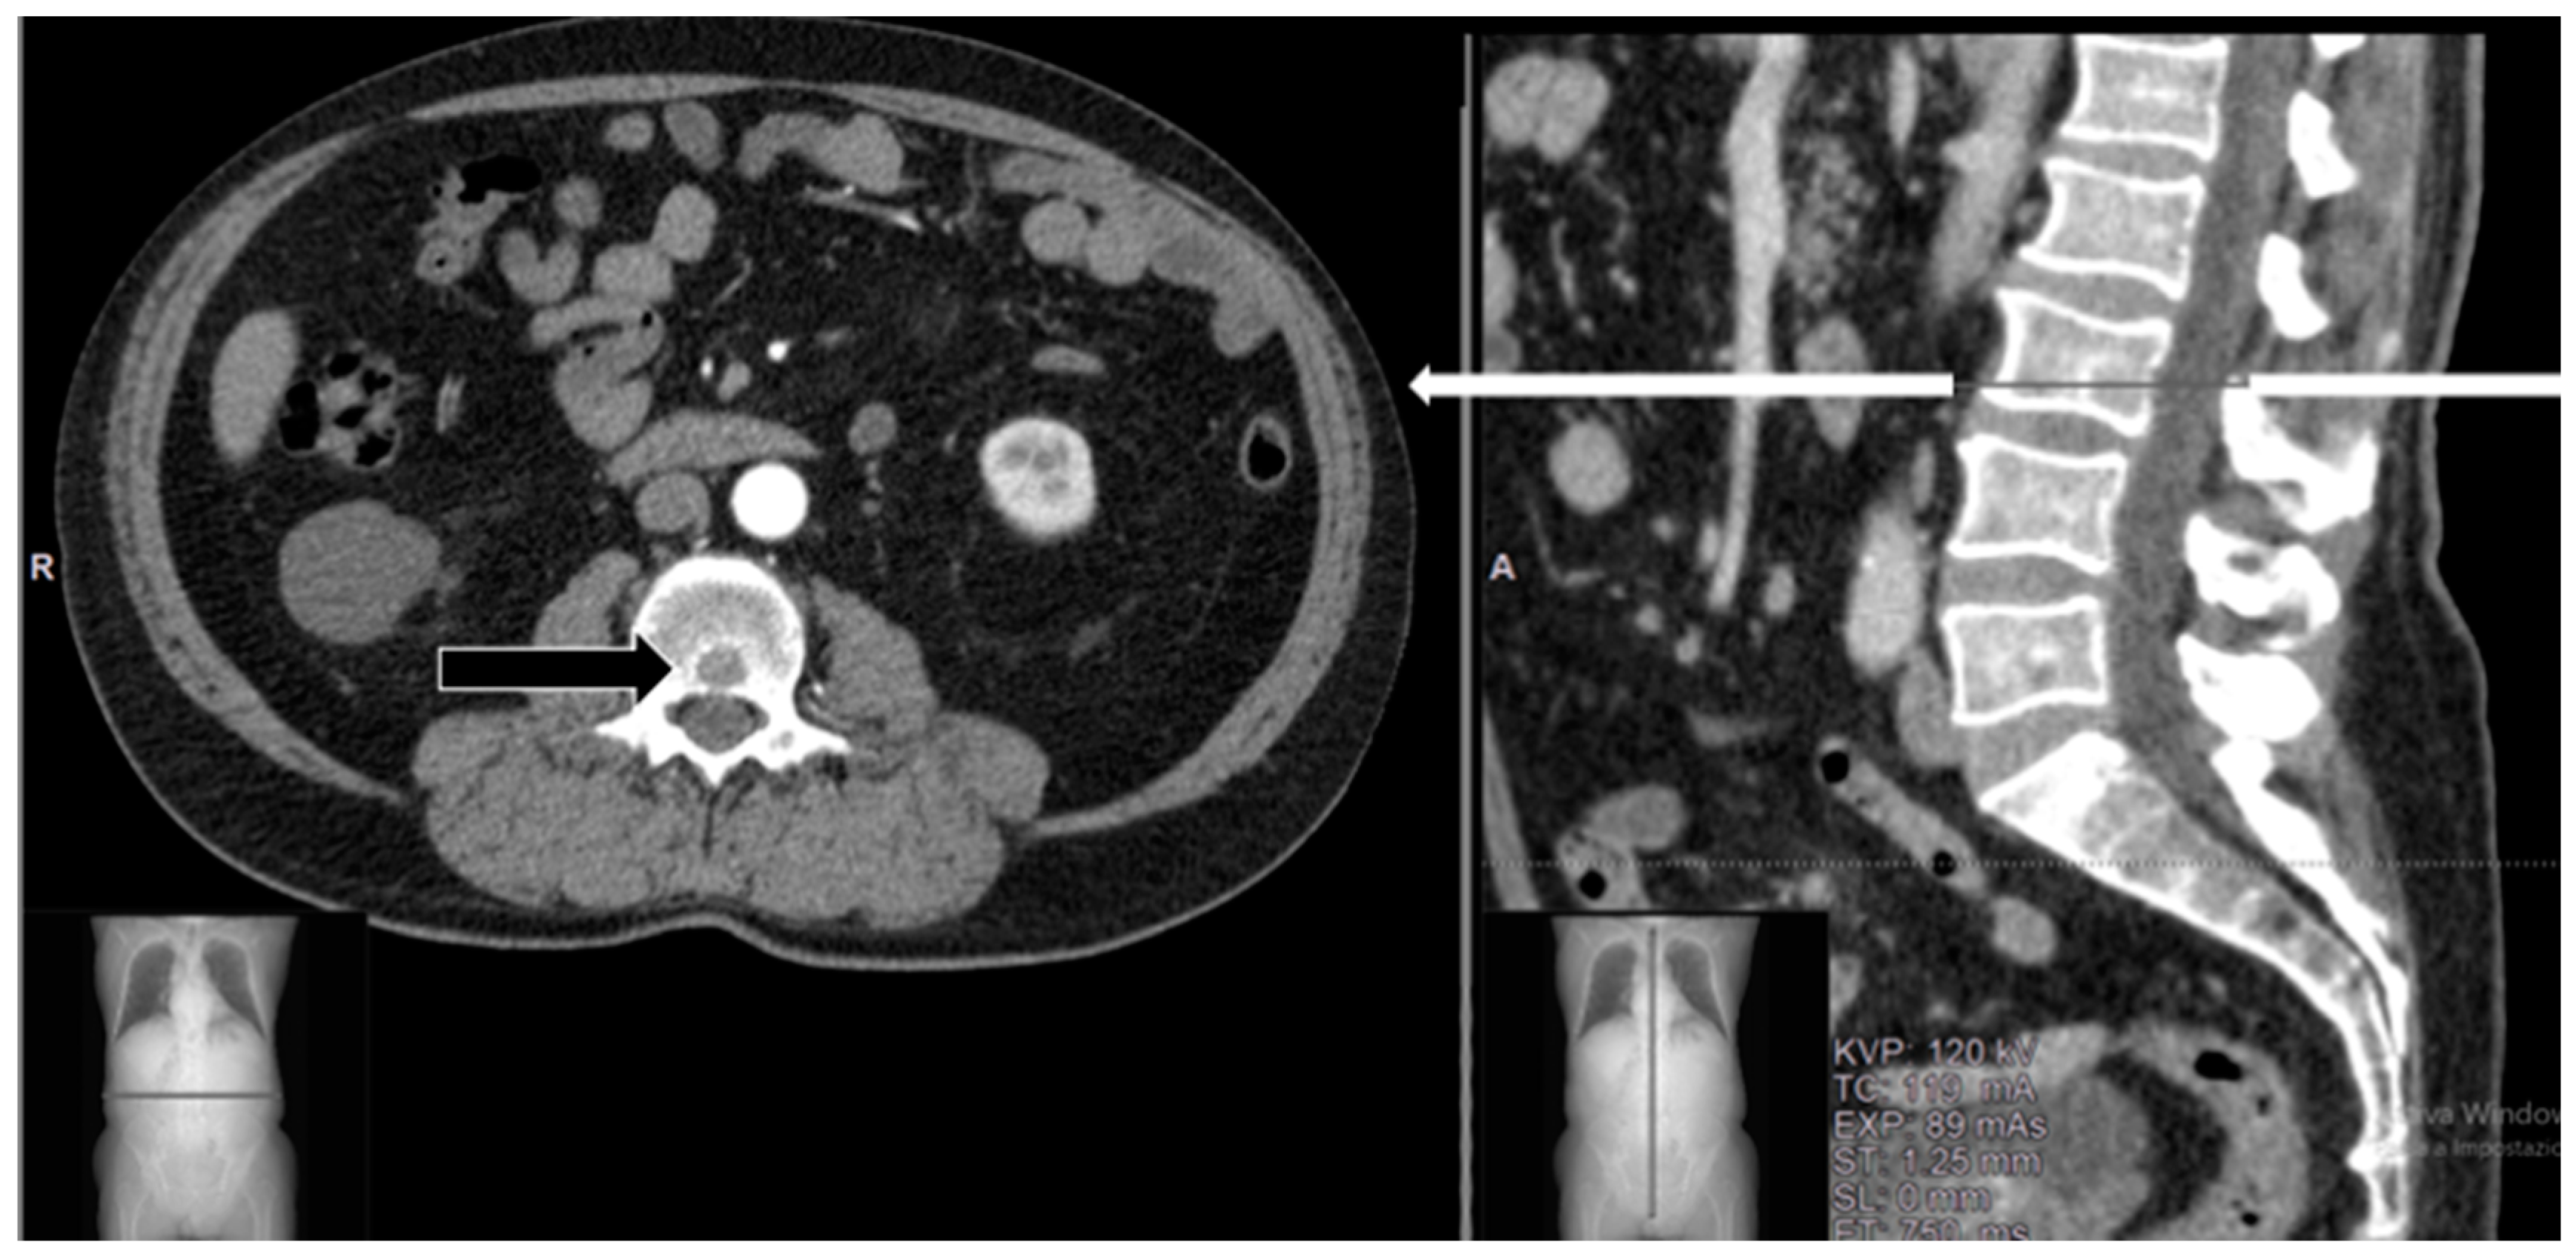

| [12] (2015) | Case report | 1 | Melanoma | Lumbar | Surgical procedure: Hemilaminectomy | Pain relief Good MRI response |

| [16] (2018) | Case reports | 2 | N/A | Lumbar Thoracic | Minimally invasive: Transpedicular Approach | N/A |

| [17] (2019) | Case reports | 2 | Breast carcinoma; Lung carcinoma | Lumbar | Percutaneous CT guided (pedicles\vertebral body) | Pain relief Good MRI response |

| [18] (2023) | Case series | 40 | Thyroid carcinoma; Lung carcinoma; Sarcoma; Others (*) | Cervical Lumbar Thoracic | Percutaneous CT guided (pedicles\vertebral body) | Pain relief Neurological improvement Good MRI response |

| Present study | Case series | 3 | Myxofibrosarcoma; Squamous cell carcinoma of skin; leiomyosarcoma | Lumbar | Transpedicular approach during surgical procedure | Pain relief and neurological improvement ** |